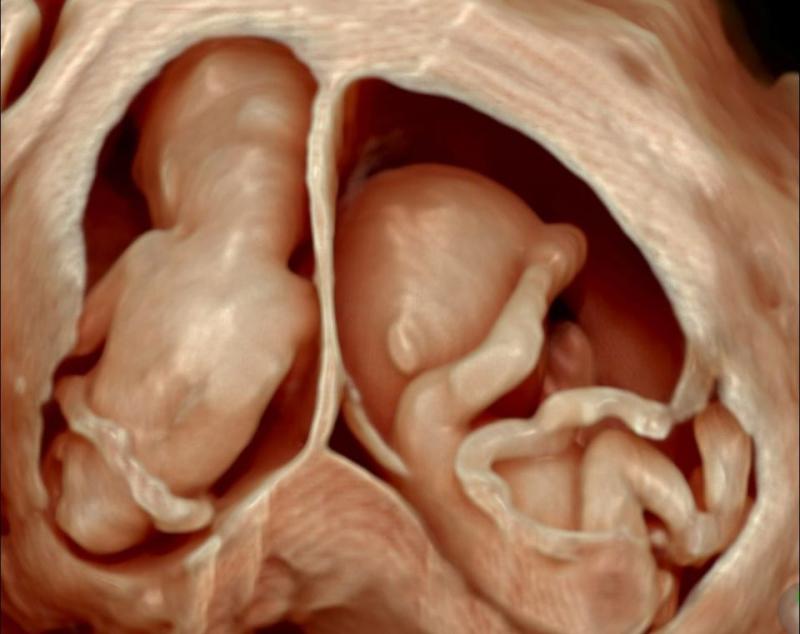

Hiện tại, bệnh viện Đa khoa tỉnh Quảng Ngãi đã được trang bị nhiều trang thiết bị y tế hiện đại như: MRI, DSA, siêu âm 3D, 4D, hệ thống xét nghiệm máy tự động đa thông số, X - quang kĩ thuật số, CT 64 lát cắt, máy siêu lọc máu, siêu âm tim gắng sức, hệ thống phẫu thuật nội soi,... góp phần trong chẩn đoán sớm và chính xác, cũng như điều trị.

Các dịch vụ sản khoa tại phòng khám bao gồm:- Siêu âm thai 3D, 4D.